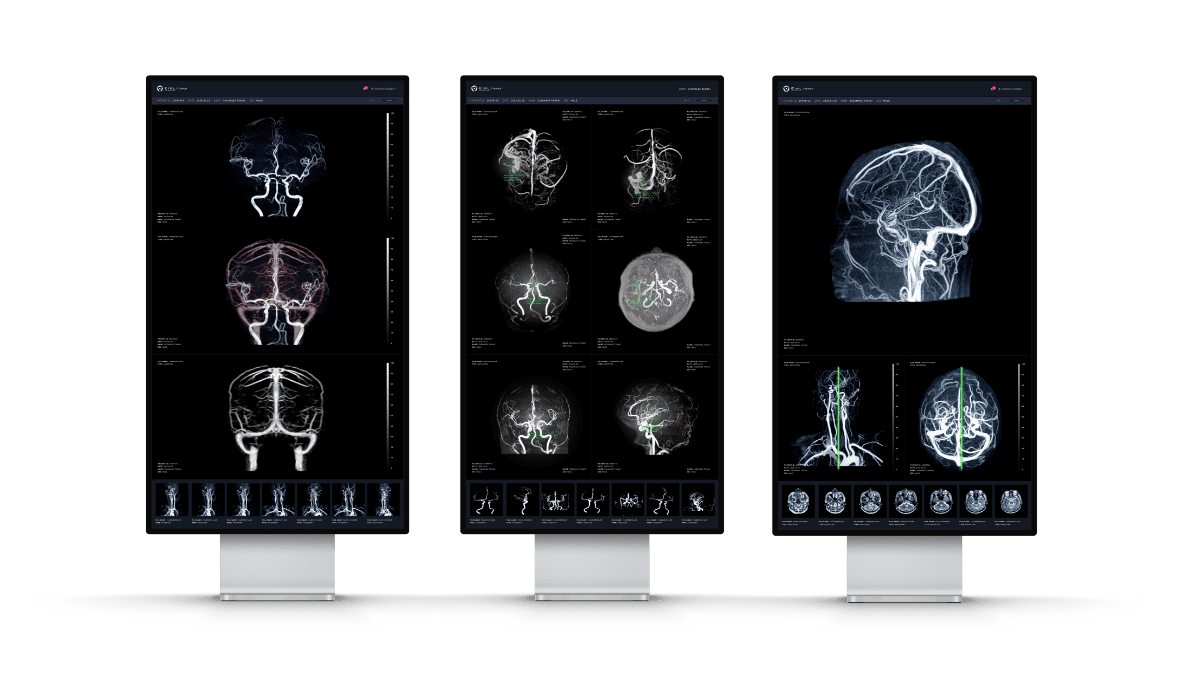

MRA診断を進化させる

脳動脈瘤検出サポートテクノロジー

脳MRA画像から嚢状動脈瘤に類似した領域(2mm以上)を検出することで、医師による読影をサポートします。本ソフトウェアを併用して読影した場合、医師単独での読影感度68.2%は77.2%に大幅に向上しました(放射線科医5年未満:69.6% → 81.2%、放射線科医5年以上:77.2% → 82.0%、脳神経外科医6年未満:53.7% → 62.3%、脳神経外科医6年以上:77.0% → 88.5%)。